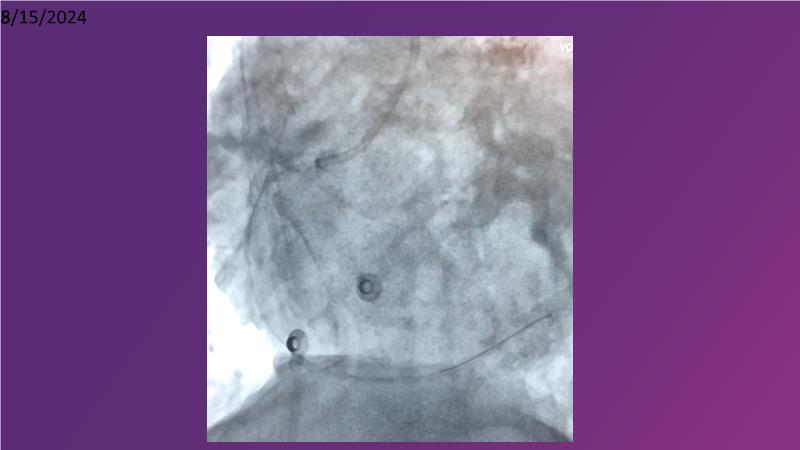

Tune into this 2024 session for insights into the latest ESC guidelines, strategies to prevent and treat no reflow, and an examination of trials like TASTE, TAPAS, and TOTAL on coronary thrombus management. Explore also the outcomes of the CHEETAH study, pondering a potential paradigm shift, and delve into a case study on thrombus removal in a patient with high thrombus burden.